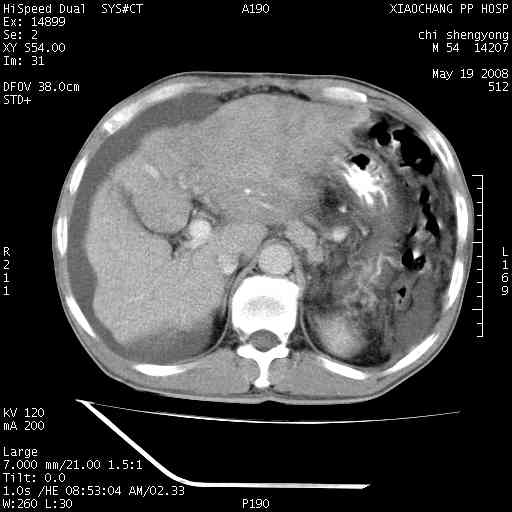

以下是引用zjzjr在2008-5-21 10:52:00的发言:[br]肝左叶巨块型肝癌伴门静脉左支瘤栓形成.肝硬化、腹水,胃底静脉曲张,脾术后改变。

以下是引用随光逐影在2008-5-21 16:20:00的发言:[br]1)肝左叶肝癌伴门静脉左支瘤栓形成,腹膜后淋巴结转移。2)肝硬化、腹水、胃底静脉曲张。3)胆囊炎。4)脾脏缺如,为切除术后所致。